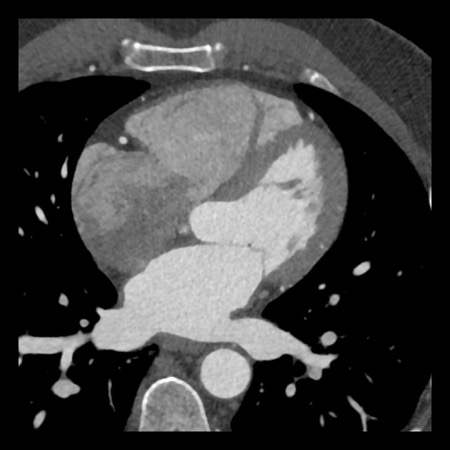

case 4 – CAD-RADS 3/P1/I+ thrombus left ventricle

First, scroll through the CTA images.

How would you describe the findings on the coronary CTA?

The findings are:

- Moderate (50-69%)

stenosis in the proximal LAD caused by a non-calcified plaque. - Variant of

sinoatrial (SA) nodal artery. The artery usually arises from the RCA as a second

branch after the conus artery, however in this case it arises from the LCX,

courses behind the aorta, anastomosing with the right atrium and with a small

branch supplies the SA-node of the heart. - Thrombus in the

apex of the left ventricle. - CTP was performed

in this patient. CTP showed a perfusion defect at stress imaging in the

territory of the LAD (I+), at rest no perfusion defect was visible.

This patient classifies as CAD-RADS 3/P1/I+, which means

this patient requires further investigation.